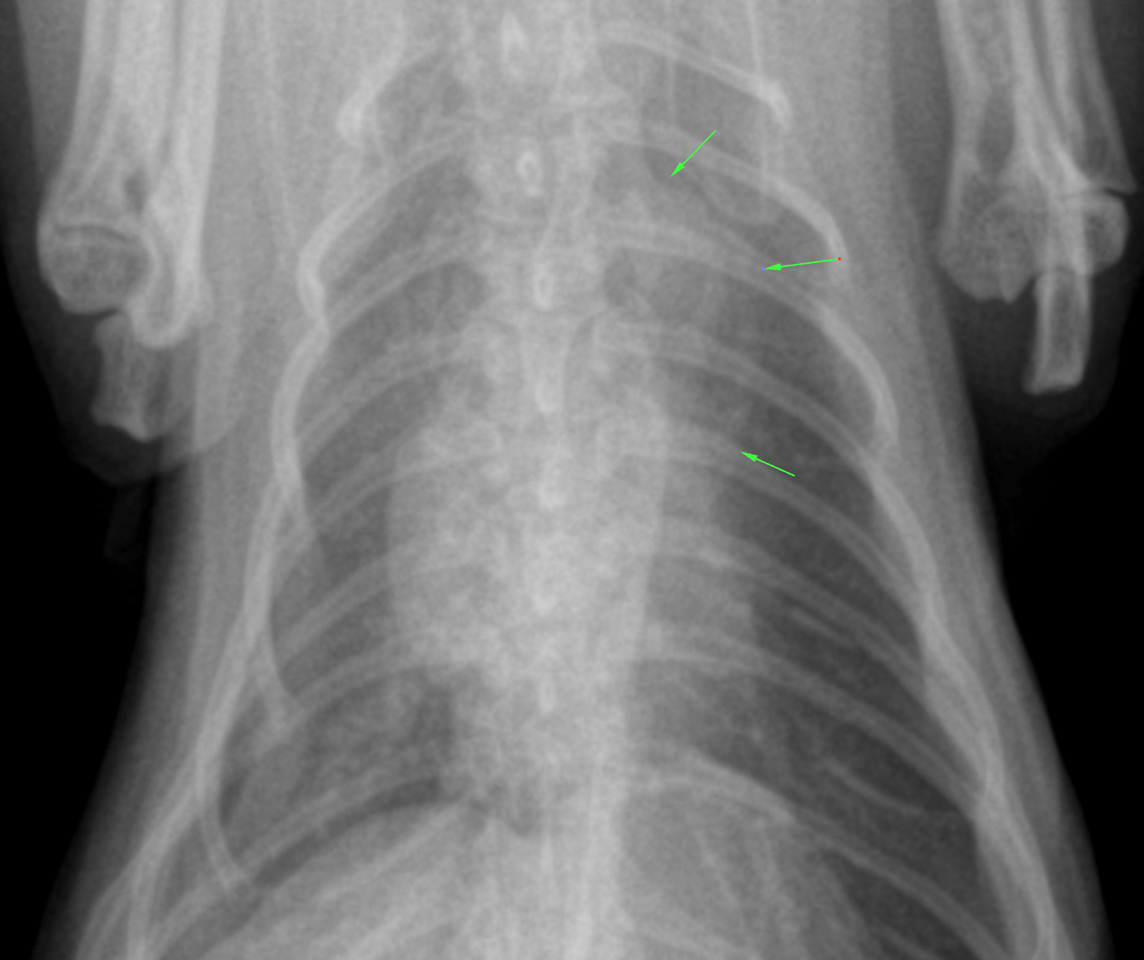

lateral and DV thorax, right lateral neck – The patient was thin.

Osseous structures:

Mild degenerative changes were associated with the axial skeleton.

Extrathoracic soft tissues:

There was aerophagia with moderate amounts of gas within the stomach and intestine. The serosal detail was mildly reduced which likely was a function of lacking peritoneal fat.

Intrathoracic structures:

The esophagus was not seen. The course of the trachea was normal. The cardiac silhouette was within normal limits. There was a redundant aortic arch. The caudal vena cava and pulmonary vessels were thin. There was no mediastinal widening.

The chest was funnel shaped. The lung presented a mild generalized thinwalled bronchointerstitial pattern. There was no air trapping. There were no signs of expiratory obstruction. There were no signs of pneumonia, congestive heart failure, pulmonary edema or pleural effusion.

DX

The lung changes are most compatible with a normal age related bronchointerstitial pattern.